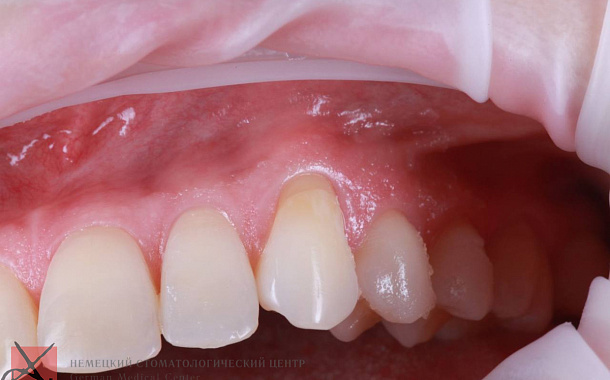

Удаление зуба и одномоментная имплантация

Пациентка обратилась в клинику с жалобами на воспаление десны в области переднего зуба верхней челюсти.

Обследование показало посттравматическую резорбция корня.

Мы удалили разрушенный корень и провели одномоментную имплантацию зуба.

Узнать подробнее